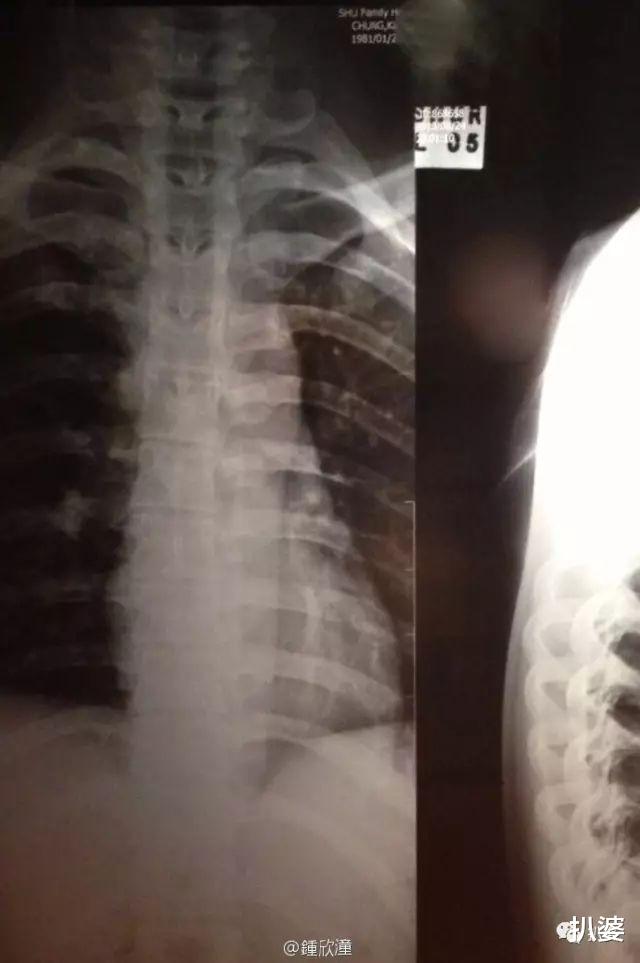

昨天凌晨 , 有媒体报道说正在厦门拍戏的阿娇钟欣潼在下榻的酒店房间发生了意外 , 并且因头部摔伤严重紧急送往医院治疗 。

事发后经纪人霍汶希和容祖儿都第一时间赶往了厦门 , 让人感觉伤势挺不乐观的样子 。

随后霍汶希发微博描述了阿娇的具体伤情 。